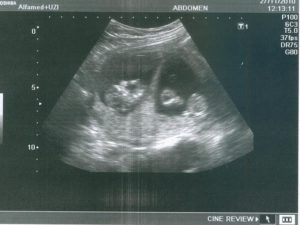

Какой вид используется для первого УЗИ при ЭКО? Поскольку от переноса эмбрионов до ультразвука проходит всего 3-6 недель, первое сканирование должно быть исключительно трансвагинальным. Только оно позволит разглядеть плодное яйцо, его нахождение и уточнить количество будущих малышей.

На этом этапе эмбрион представляет собой крошечный шар с едва различимыми головным и хвостовым концами, окруженный плодным яйцом. УЗИ-диагностика на ранних сроках беременности проводится двумя способами:

Именно УЗИ на третьей неделе после введения эмбрионов является методом, позволяющим достоверно определить наличие беременности, так как ЭКО, к сожалению, не всегда может гарантировать удачный результат.

Кроме того с помощью ультразвукового сканирования можно увидеть:

- Количество жизнеспособных эмбрионов в матке;

- Место расположения плодного яйца;

- Изменения в яичниках.